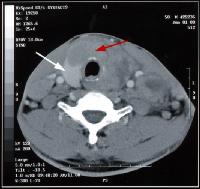

CT-Scan van de hals

Bedoeling van een scan van de hals kan zijn, het opsporen van een defect ter hoogte van de bloedvaten van de hals, of een abnormaal voorkomen van een bepaalde structuur in de hals, vb. een vergrote schildklier.

Een CT-scan van de hals wordt meestal uitgevoerd met contrast.

Uitzonderingen hiervoor zijn de onderzoeken van de schildklier.